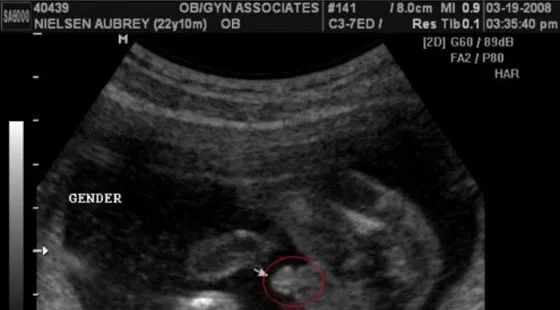

男宝宝四维彩超图

“凸出的东西” 是他的标记: 你们看到圆圆的是蛋蛋,如果看到圆圆的加小肠的就是全部JJ